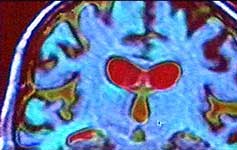

|  |  | The Neuro-anatomy of the Moral Mind

In this week's Leading Edge Geoff Watts talks to moral philospher-turned-neuropsychologist Joshua Greene at Princeton University about his research using functional Magnetic Resonance Imaging (MRI) to watch the brain activity of people making different kinds of moral judgements. In one experiment, Greene and his team gave a series of moral dilemmas for subjects placed in the MRI scanner to ponder. There were two categories of moral problem that they were particularly interested in comparing which the team have labelled impersonal and personal respectively.

For the majority of people, the 'personal'-style of dilemma is a greater challenge and they tend to take much longer to make a decision. In the MRI scans, the impersonal tends to result in an increased activity in abstract reasoning parts of the brain whereas the second 'personal' dilemma results in a more complicated pattern. In people who ponder this for sometime before making a decision, brain areas linked to social and emotional behaviour increase in activity as well as the abstract reasoning areas, together with an area (the anterior singulate cortex) which is active when different urges are in conflict.

Joshua Greene interprets the observations in terms of two mental domains of different evolutionary age in conflict - the ancestral primate social-emotional mind (which he says recoils from pushing the man off the bridge) and the more recently evolved abstract-reasoning capacity which is doing the Utilitarian numbers game. He believes an understanding of how our brains deal with moral judgements may help to us to make 'better' moral decisions.